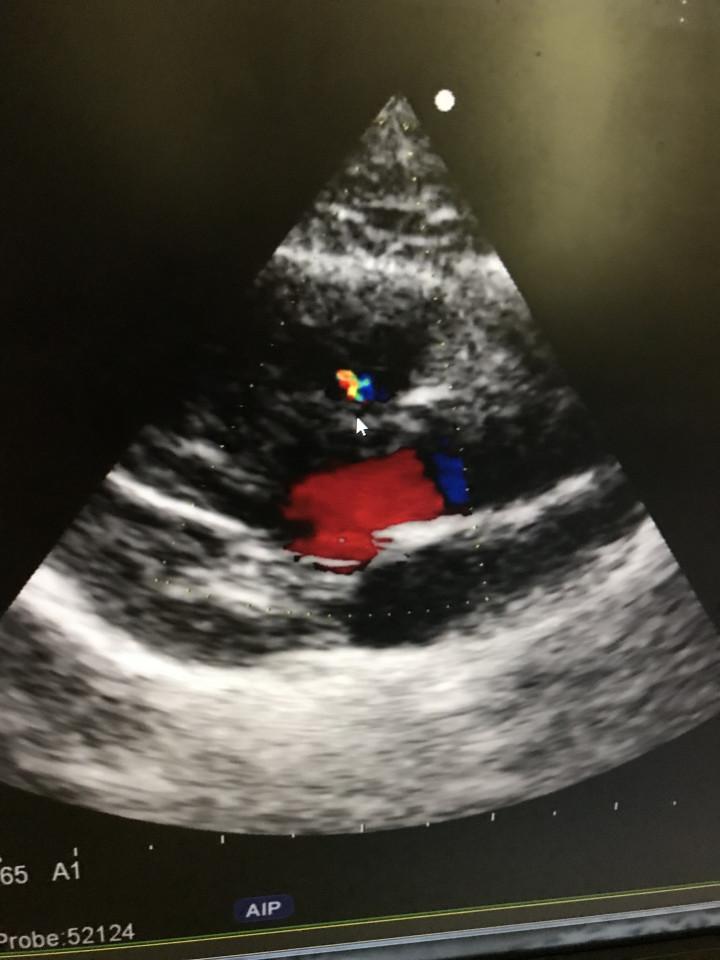

あれだけ流れ出ていた血液が、こんなに少なくなりました!

黄色と緑がほとんど見えません。

奇跡的に穴を塞ぎ始めた繊維化した組織。

先生が『もう大丈夫❗️』って、太鼓判を押してくれました🙌🙌🙌